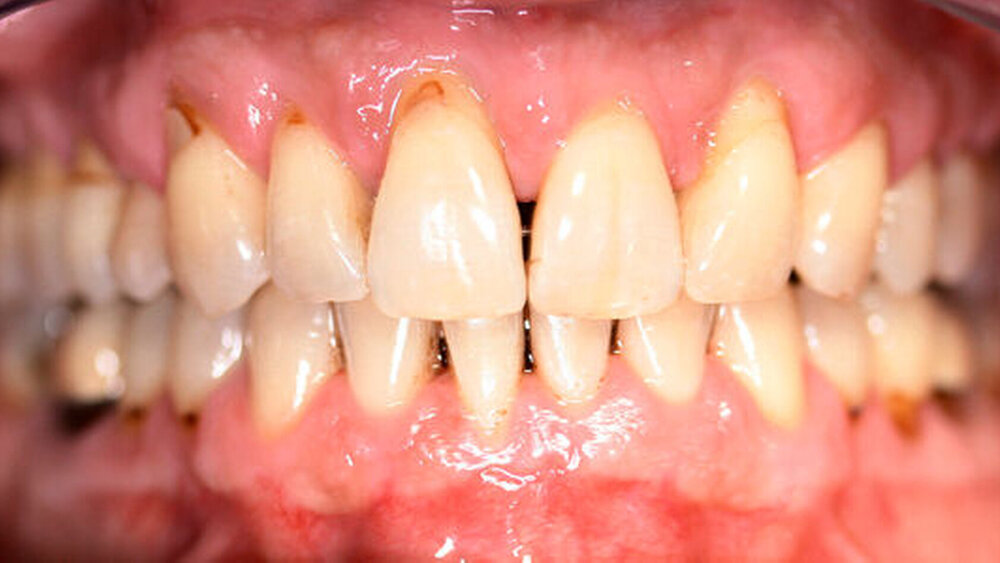

Nach erfolgter Parodontitistherapie und konservierender Versorgung stellte sich der Patient Ende 2014 erneut in unserer Praxis vor.

Die Sulkustiefen konnten auf etwas weniger als 4 mm reduziert werden, während der Blutungs- und Plaque-Index bei weniger als 15 Prozent lag. Daher wurde eine kieferorthopädische Behandlung über die nächsten zwei Jahre in Kombination mit engen zahnärztlichen Kontrollen geplant. Als Mittel der Wahl entschieden wir uns gemeinsam mit dem Patienten für das Invisalign-System, da hiermit sowohl eine Schienung als auch eine kraft-arme Bewegung der Zähne möglich sein sollte. Für den Frontzahnbereich wurden keine Attachments geplant, so dass hier eine unnötige Hebelwirkung umgangen werden konnte (Abbildung 3).